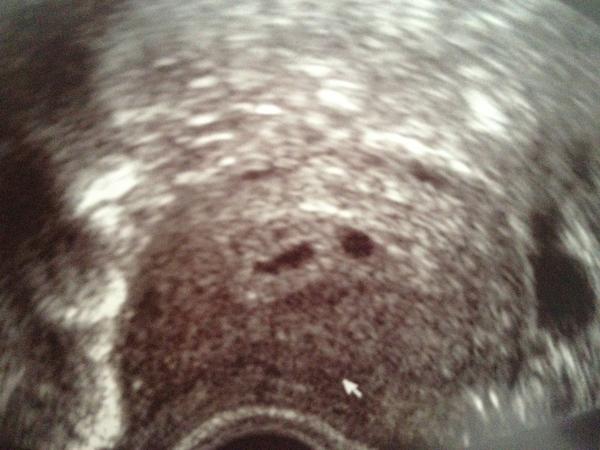

Ultrazvuk za mnou a jsou tam opravdu oba broučci!!!!! Jsem strašně šťastná 😵

@cilkaa Evíku ja byla taky paf,myslela jsem že budu bulet jak želva,jen mně to bylo blbe před plnou čekárnou.Pak jsem byla pár dnu jak mimon uplně roztěkaná,jak byla další kontrola a tukala srdíčka už jsem se usmívala,ale obavy jsou pořád,už kapku menší,ale jsou ted se blíží velky UTZ ve 20ttTak z toho mám ještě bobky,pak už to snad bude lepší.Navíc už prdelky občas během dne postřehnu jek se zavrní je to o dost lepší. 😉